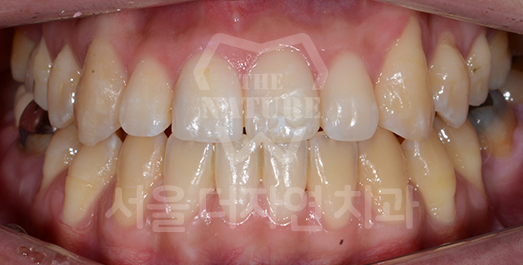

Crowding (Supernumerary / Overlapping Teeth) Solution

Crowding occurs when there is insufficient space for teeth to erupt into proper position. If left untreated for a prolonged period, inadequate brushing access leads to food impaction between teeth and a significantly elevated risk of dental caries. As crowding is also a contributing factor to periodontal disease,

orthodontic correction is strongly recommended.

• BEFORE: 2020.06.11

• AFTER: 2023.02.02